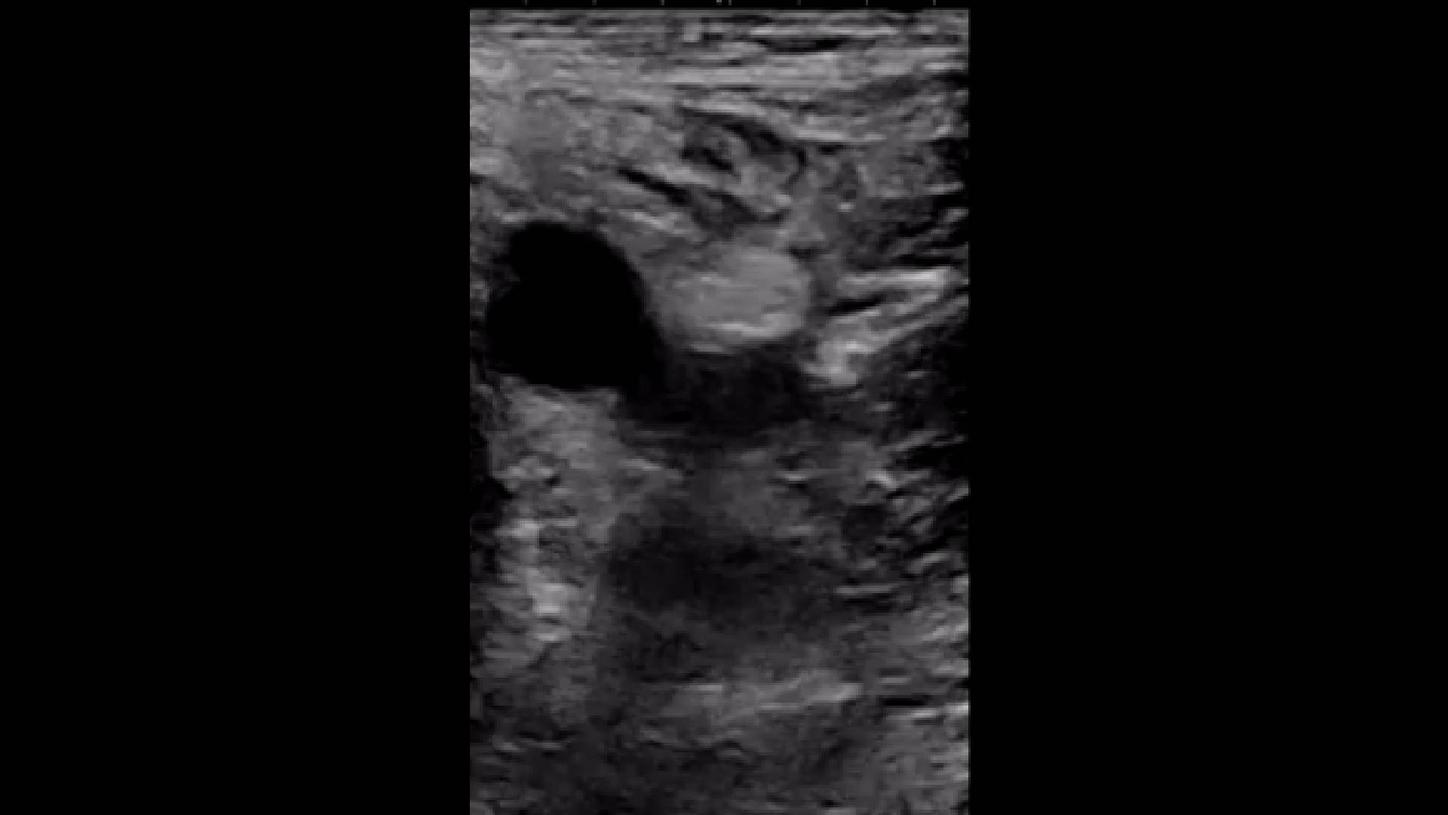

Objetivo clínico: Integración facilitada del ultrasonido como herramienta para ayudar a reducir las complicaciones vasculares.

Soluciones y características seleccionadas: ACUSON Freestyle, Una sonda de ultrasonido inalámbrica, integrada con el ARTIS pheno, se utiliza para realizar el acceso transfemoral. Se ha demostrado que la cateterización de la arteria femoral guiada por ultrasonido ahorra hasta un 92% en el tiempo de preparación del campo estéril y reduce las complicaciones relacionadas con la punción en un 49%².